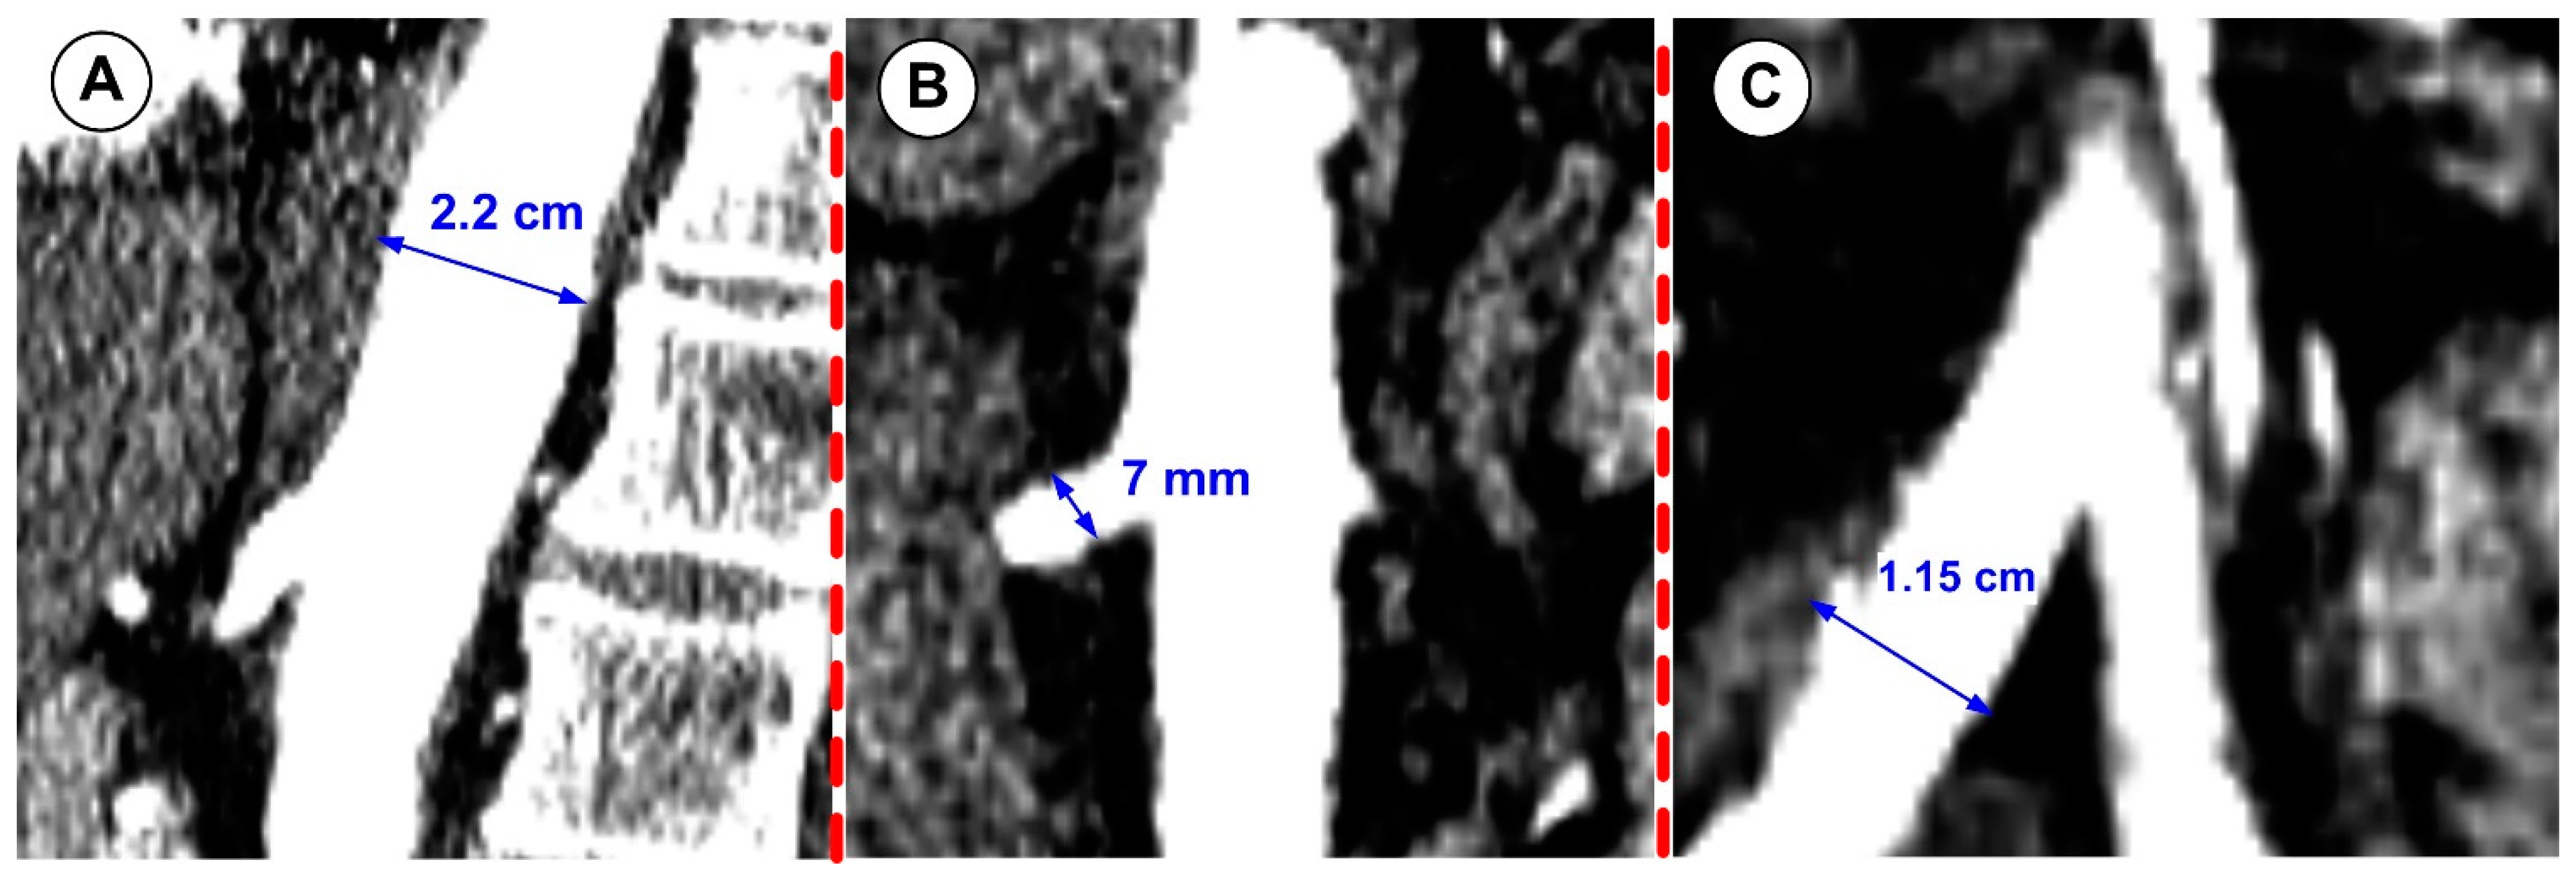

| Aorta (inlet section) | 22.00 | 14–30 | [29] |

| Celiac artery | 7.16 | 8.57 ± 1.57 | [30] |

| Superior mesenteric artery | 7.84 | 8.35 ± 1.60 | [30] |

| Left renal artery | 7.12 | 7.03 ± 1.40 | [30] |

| Right renal artery | 7.00 | 7.13 ± 1.20 | [30] |

| Inferior mesenteric artery | 4.04 | 4.21 ± 1.20 | [30] |

| Left iliac artery | 11.00 | 11.77 ± 2.20 | [30] |

| Right iliac artery | 10.90 | 12.23 ± 2.40 | [30] |